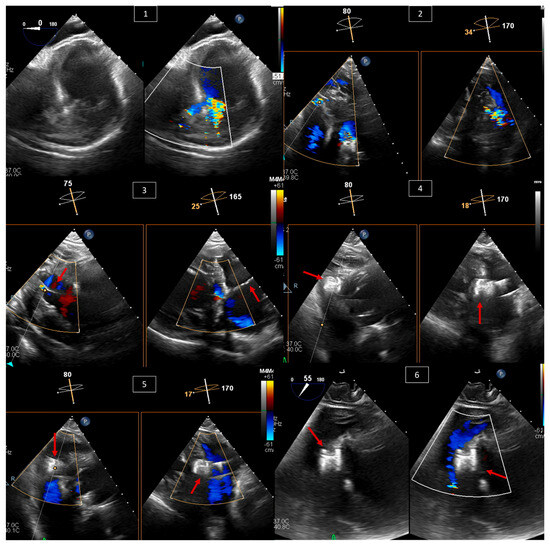

2. Atrial Septal Defect (ASD) and Patent Foramen Ovale (PFO) Closure

3. Ventricular Septal Defect (VSD) Closure